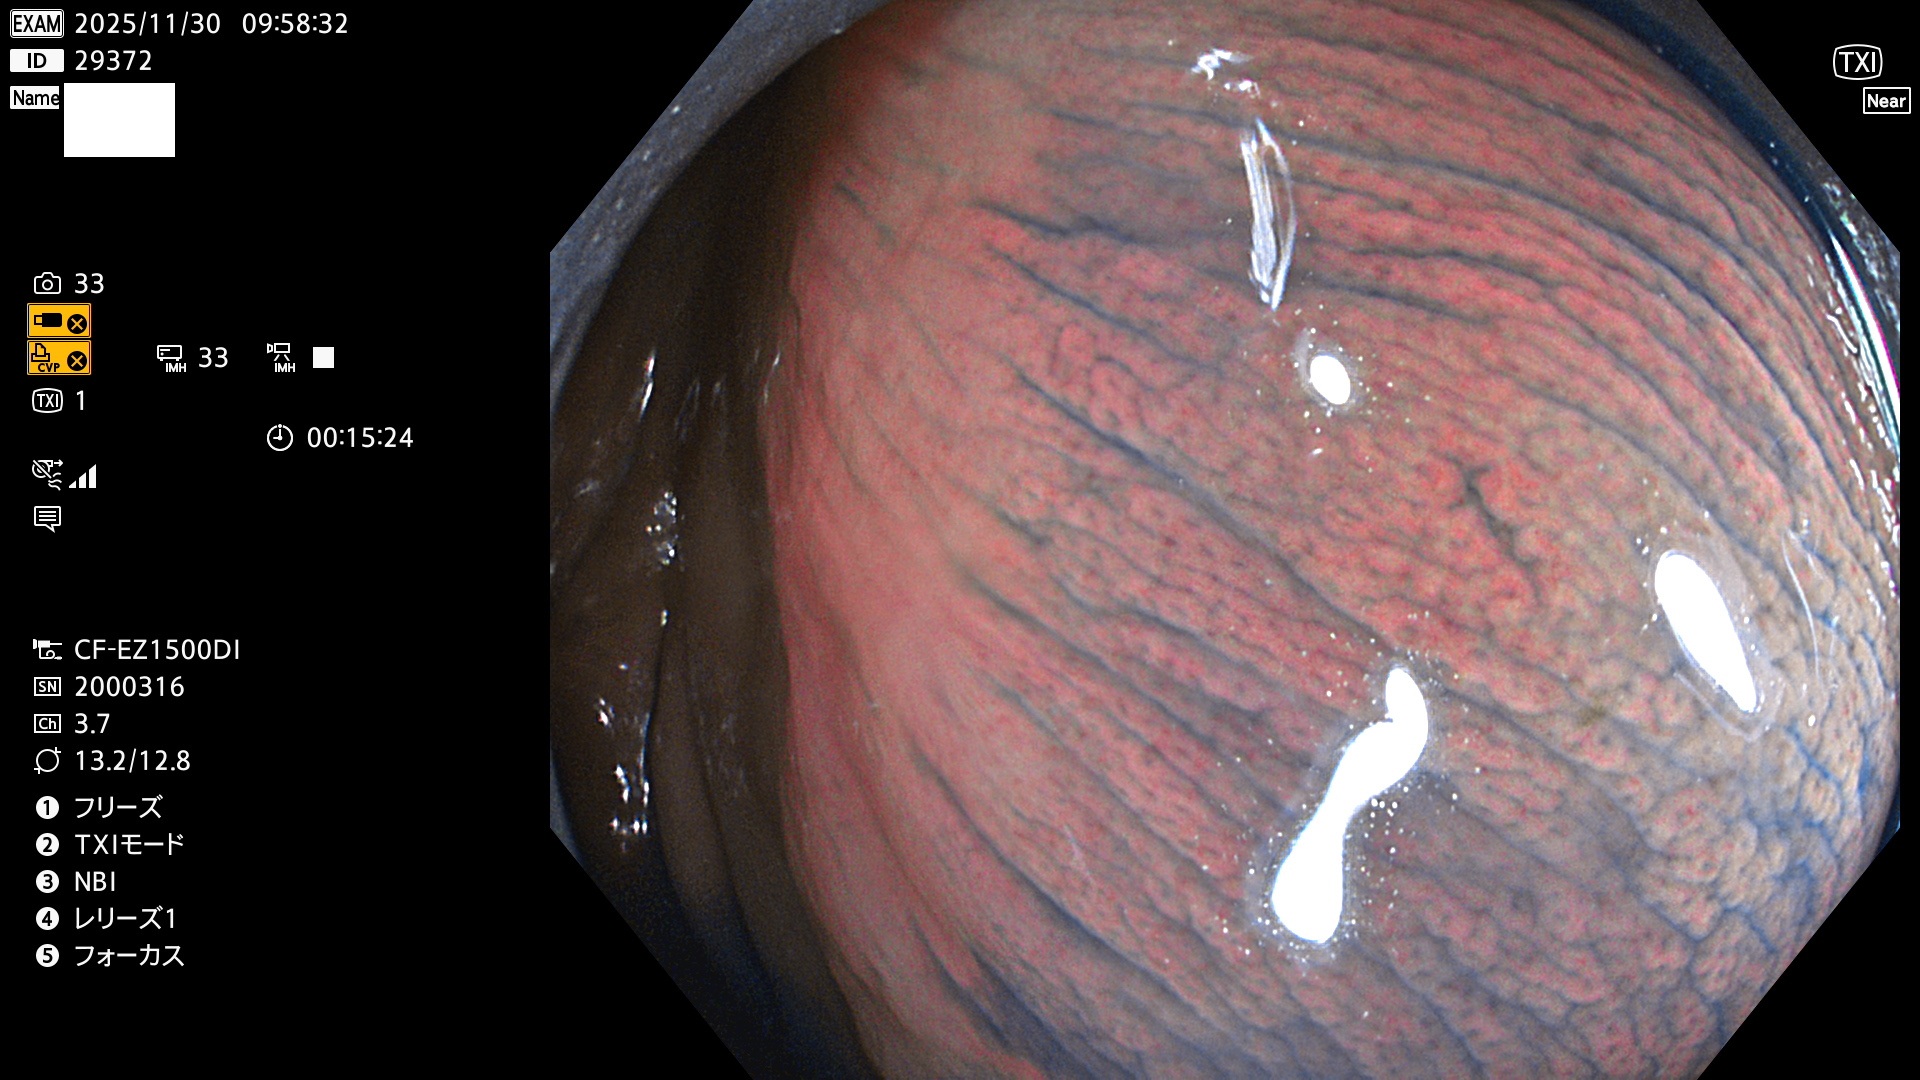

完全に平坦な物をUb、陥凹している物をUcと呼びます。Ubは認識が困難で、Ucはびらん(炎症)と紛らわしいために見落とされやすく、「内視鏡後・大腸癌」の原因になります。

毎週の検査(木・金・土・日)に発見されたUbとUc型・腺腫を、その週の日曜の夜にUPし1週間、提示します。

2025年11月27日〜12月7日の7日間(70件)6個 (Uc_ADR=6個/70人=9%)